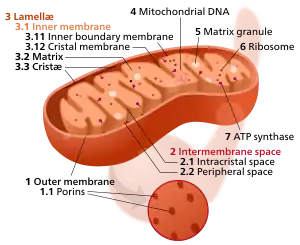

Mitochondrial dysfunction

The mitochondrion is the powerhouse of the cell. Different human cells contain from several up to 2500 mitochondria,[31] each one converting carbon (in the form of acetyl-CoA) and oxygen into energy (in the form of ATP) and carbon dioxide.

During aging, the efficiency of mitochondria tends to decrease. The reasons for this are still quite unclear, but several mechanisms are suspected: reduced biogenesis,[32] accumulation of damage and mutations in mitochondrial DNA, oxidation of mitochondrial proteins, and defective quality control by mitophagy.[33]

Dysfunctional mitochondria contribute to aging through interfering with intracellular signaling[34][35] and triggering inflammatory reactions.[36]